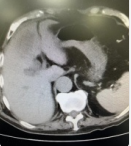

20221110日再次复查腹部CT:肝右叶区域团块影,考虑感染性病变,目前病变较前明显减少。